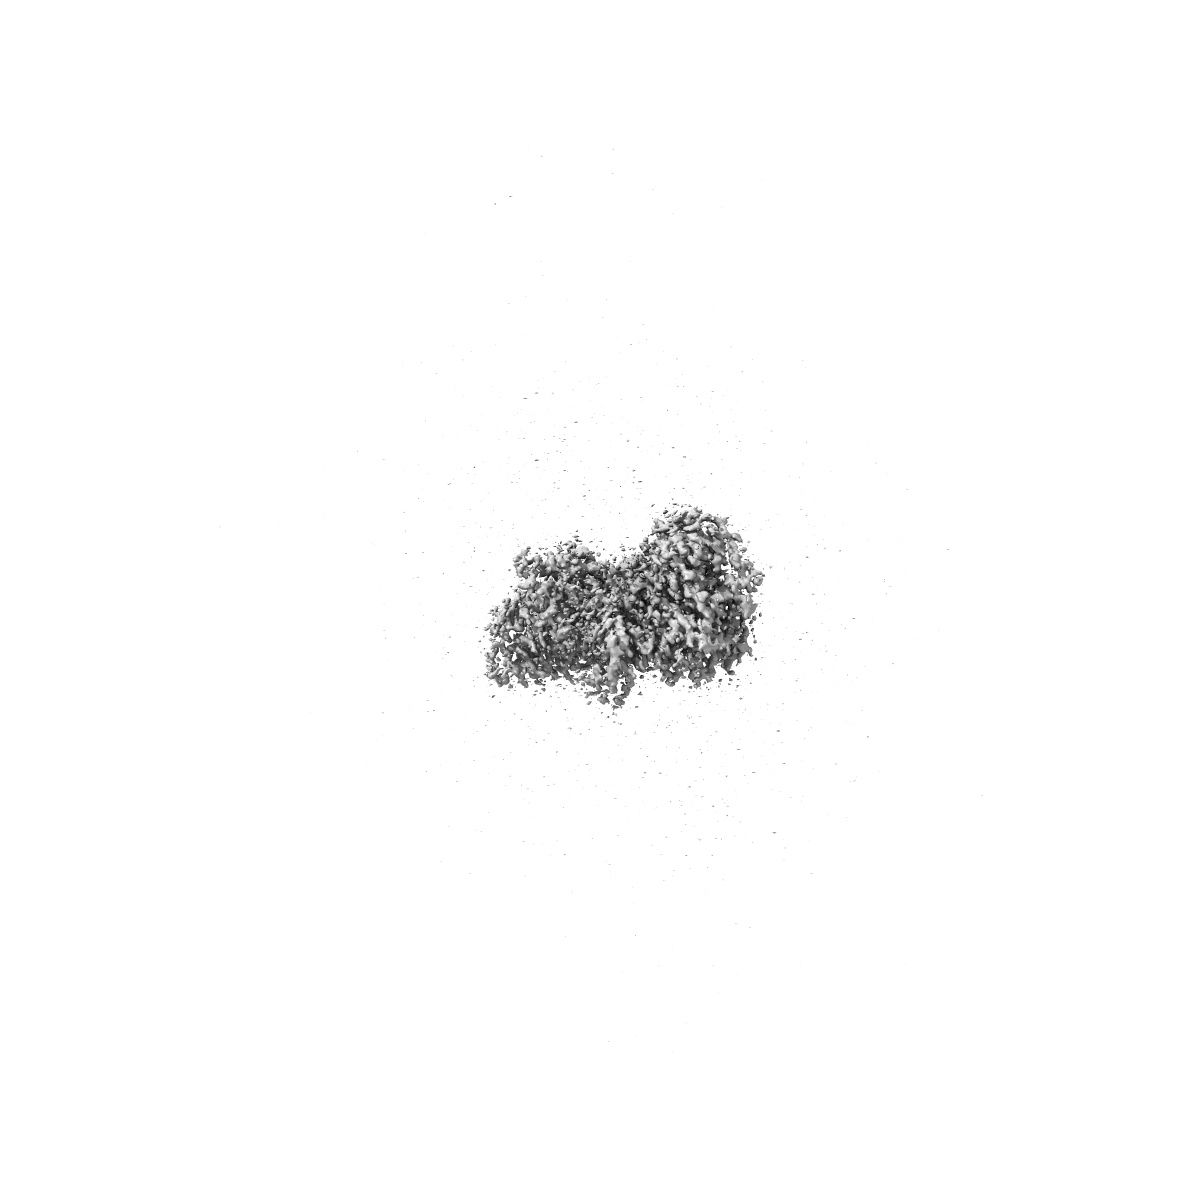

Cryo-EM structure of CAK in complex with inhibitor dinaciclib

Single-particle1.9 Å

Sample: CDK-activating kinase

High-resolution cryo-EM of the human CDK-activating kinase for structure-based drug design.